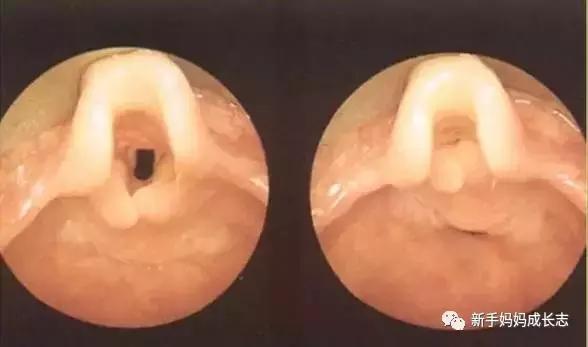

我们先来看看正常结构什么样

如果出现喉软化症,就会出现会厌的塌陷